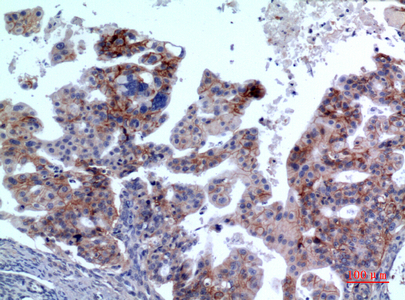

![IL1 Receptor 2 antibody [N3C3] detects IL1 Receptor 2 protein at cytoplasm in human colon cancer by immunohistochemical analysis. Sample: Paraffin-embedded human colon cancer. IL1 Receptor 2 antibody [N3C3] (GTX108702) diluted at 1:500.

Antigen Retrieval: Citrate buffer, pH 6.0, 15 min](https://www.genetex.com/upload/website/prouct_img/normal/GTX108702/GTX108702_40016_20150420_IHC_2_w_23060120_741.webp)